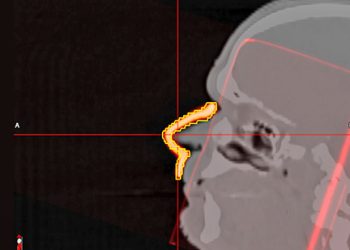

Read moreNorth Texas VA recently introduced a breakthrough in cancer treatment for Veteran patients with the unveiling of a new molecular...